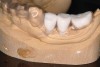

Figure 4  Computer-guided surgical template.

Figure 4

A surgical guide, based on the 3-dimensional implant locations is fabricated for use in conjunction with the selected implant manufacturer's guided surgery instrumentation (Figure 4). Using this template, safe implant positioning in all three dimensions is performed, avoiding trauma to vital anatomic structures respecting the restorative outcome prescribed prior to surgery (Figure 5 and Figure 6). Following 8 weeks of transmucosal healing time, standard restorative therapy is initiated (Figure 7).